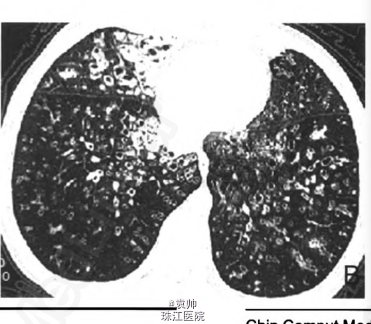

4个月后症状明显好转,复查肺部CT:双肺部结节状阴影明显减少(图1B)。弥漫性泛细支气管炎(diffuse panbronchiolitis,DPB)是一种弥漫存在于两肺呼吸性细支气管的气道慢性炎症,受累部位主要是呼吸性细支气管以远的终末气道。由于炎症病变弥漫性地分布并累及呼吸性细支气管壁的全层,故称为DPB。临床上多表现为咳嗽、咳痰和运动后气促,可表现为慢性鼻窦炎和慢性支气管炎,严重者可导致呼吸功能障碍。DPB在我国不常见,其发病率较低,故目前误诊率较高,易被误诊为支气管扩张、慢性支气管炎或肺间质纤维化等疾病。目前本病在国际上尚无统一的诊断标准,我国主要参考日本1998年第二次修订的临床诊断标准,诊断项目包括必须项目和参考项目。必须项目:①持续咳嗽、咳痰及活动时呼吸困难;②合并有慢性副鼻窦炎或有既往史;③胸部x线平片见两肺弥漫性散在分布的颗粒样结节状阴影或胸部CT见两肺弥漫性小叶中心性颗粒样结节状阴影。参考项目:①胸部听诊断续性湿罗音;②1 s用力呼气容积占预计值百分比(FEVl占预计值%)70%以及低氧血症(PaO2,<80mmHg);③血清冷凝集试验效价增高(1:64以上)。确诊需符合全部必须项目及参考项目中的2项以上。可疑诊断需符合必须项目1和2。如能早期诊断,早期治疗,DPB是可以治愈的。【摘自:《中国医学计算机成像杂志》2012,18:561-562《弥漫性泛细支气管炎1例病例报道及文献复习》】